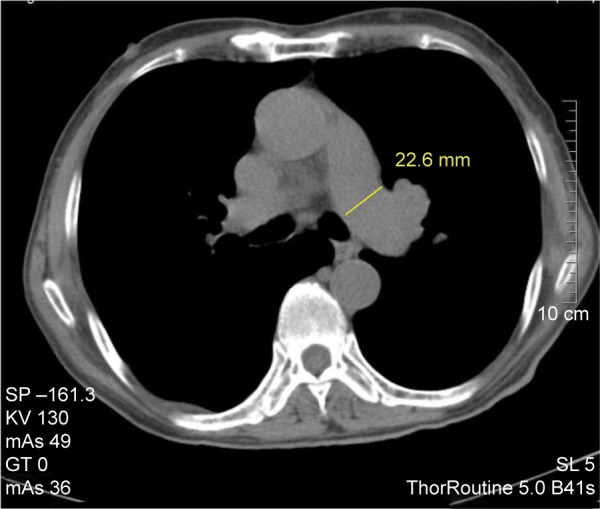

Computed tomography (CT) is widely used for evaluation of lung diseases. To evaluate the value of CT measurement of pulmonary artery for diagnosis of chronic obstructive pulmonary disease (COPD) and its comorbidity pulmonary hypertension (PH), we retrospectively reviewed the CT of 221 patients with COPD and 115 control patients without cardiovascular or lung disease. Patients with COPD were divided into PH (COPD-PH) and non-PH according to systolic pulmonary artery pressure. Main pulmonary artery (MPA), right pulmonary artery (RPA) and left pulmonary artery branches, and ascending aorta (AAo) and descending aorta (DAo) diameters were measured. Meanwhile, the ratios of MPA/AAo and MPA/DAo were calculated. MPA, RPA, and left pulmonary artery diameters were significantly larger in COPD than those in the controls, and this augment was more obvious in COPD-PH. AAo and DAo diameters did not vary obviously between groups, while MPA/AAo and MAP/DAo increased significantly in COPD and PH. MPA could be helpful for COPD diagnosis (MPA diameter ≥27.5 mm, sensitivity 54%, and specificity 80%), and RPA could be applied for COPD-PH diagnosis (RPA diameter ≥23.4 mm, sensitivity 67%, and specificity 76%). There was a marked correlation between MPA/DAo and systolic pulmonary artery pressure (r=0.594, P<0.001). Therefore, chest CT could be a simple and effective modality for diagnostic evaluation of COPD and its comorbidity, PH.

Abstract Image